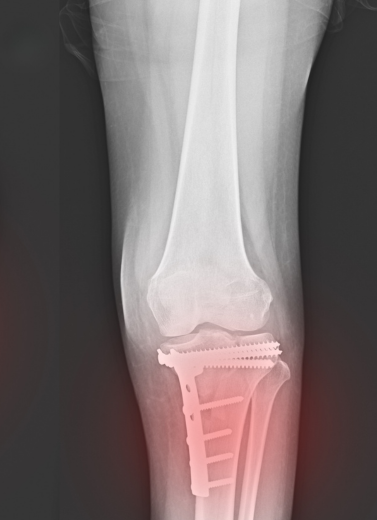

Plating & Nailing Techniques

All surgeries are performed with infection-controlled OTs, digital X-ray support, and post-op rehab planning.

We treat each trauma case with urgency and care, beginning with imaging (X-ray/CT), followed by a personalized treatment plan. Whether surgical or conservative, our aim is quick stabilization, early mobilization, and pain control.